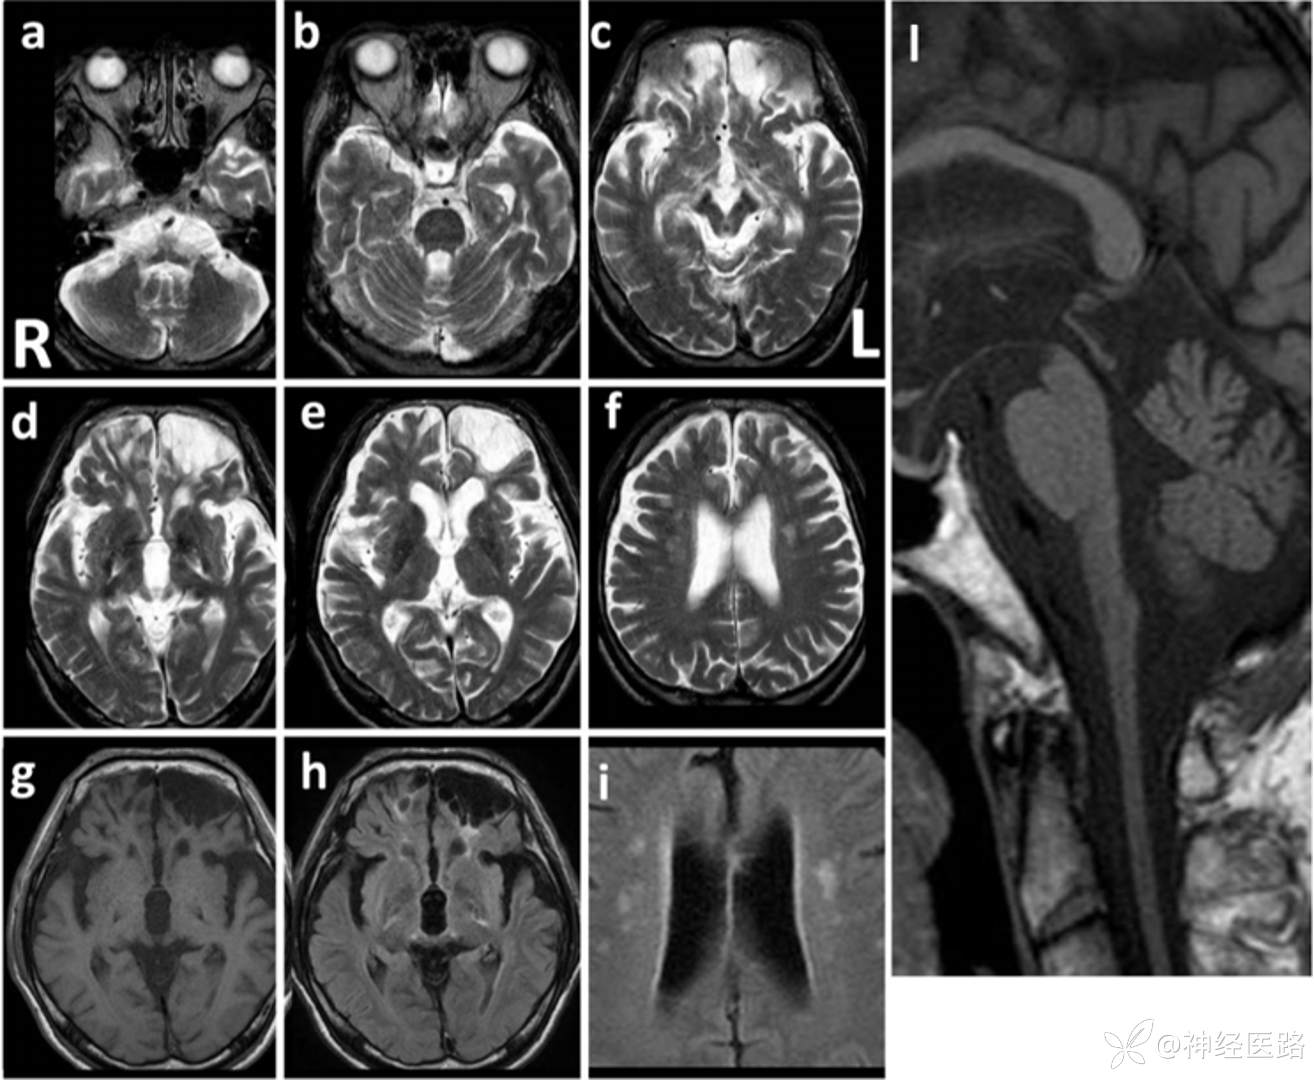

AxD脑磁共振最典型表现是额叶为主的脑白质营养不良,在婴儿型中最为典型。但II型成人多见,影像学表现不典型,幕上脑白质改变不突出,表现为下位脑干至颈髓萎缩,表现“蝌蚪征”。桥臂基本不萎缩。

a:延髓明显萎缩 a、b:小脑轻度萎缩 c:中脑背部萎缩 l:典型的蝌蚪样脑干萎缩(构成包括延髓颈髓明显的萎缩、完整的桥脑基底部)

成人亚历山大病临床表现多样,影像以延髓和高颈髓萎缩为特点。